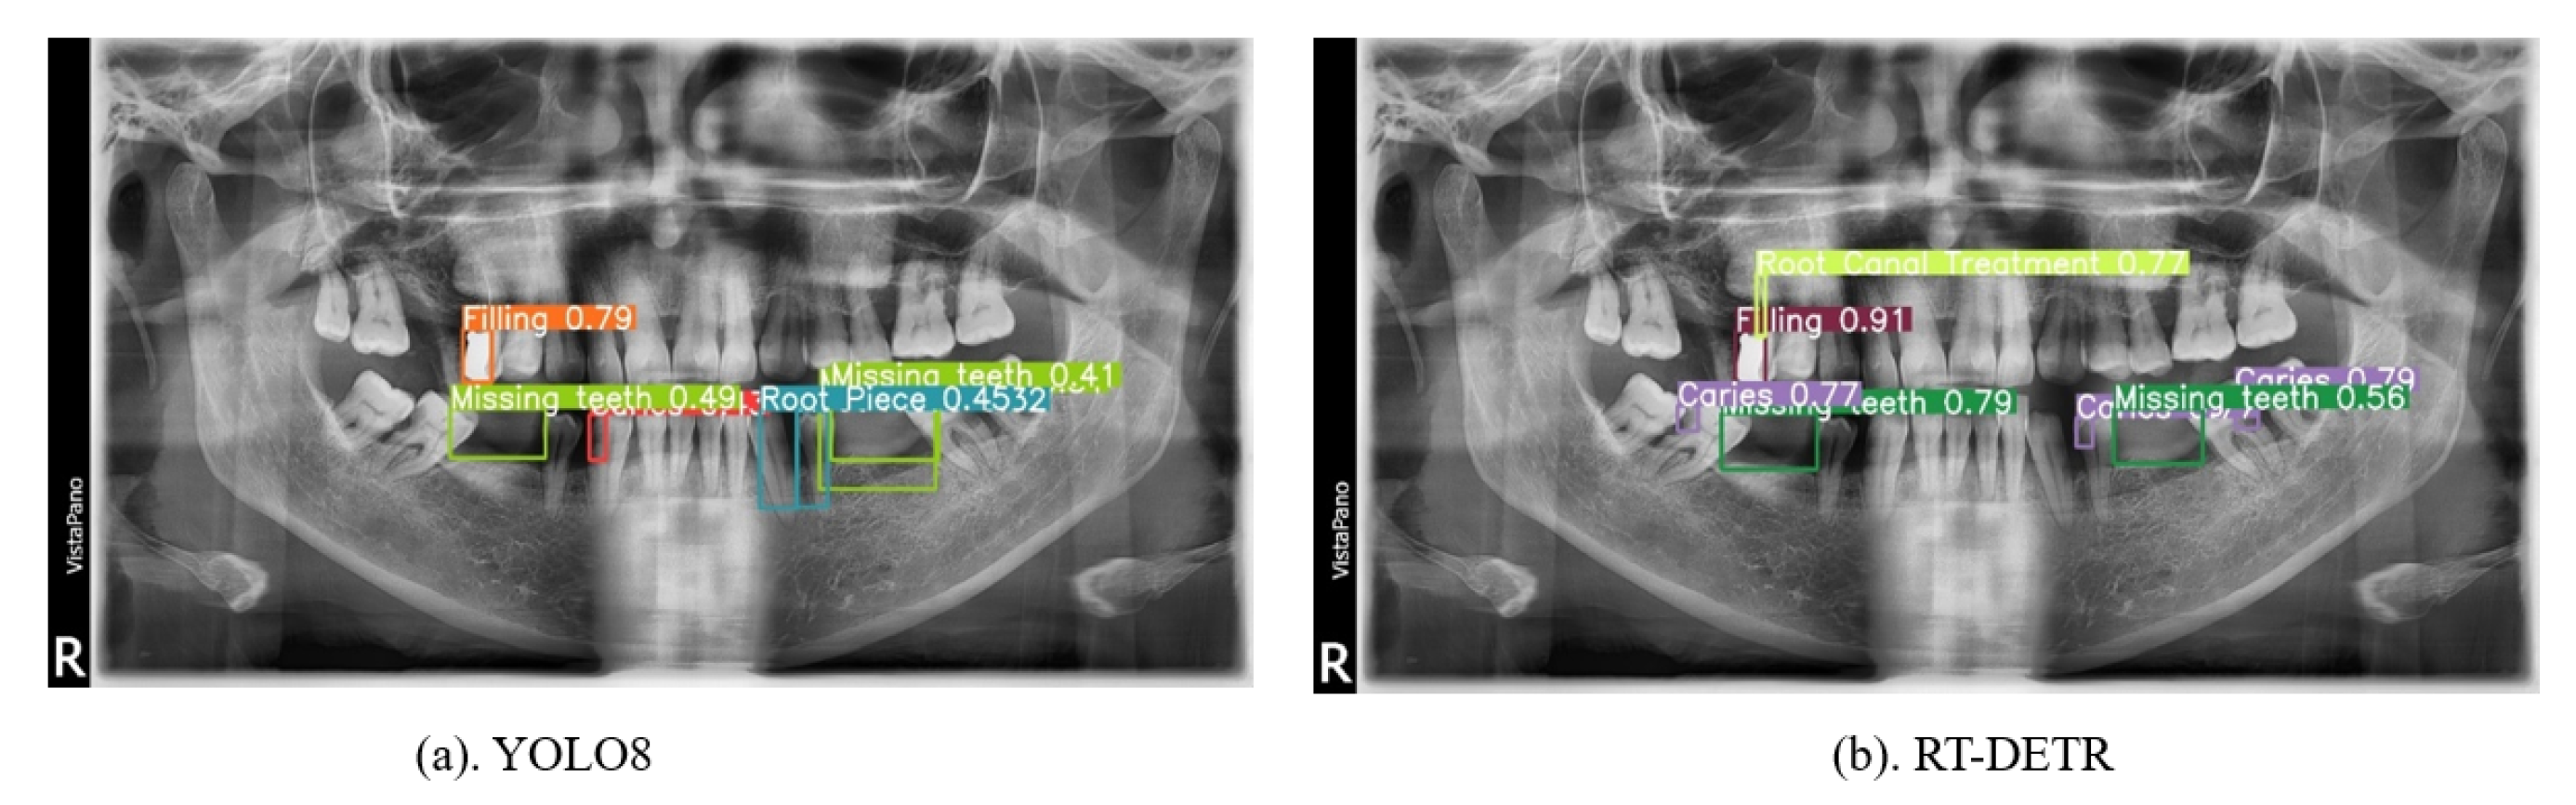

| Position of Image | YOLO8 | RT-DETR | Ensemble |

|---|---|---|---|

| Top Row | - “Filling” with a confidence score of 0.79. | - “Filling” with confidence scores of 0.91 and 0.43. | - “Filling” with a confidence score of 0.91. |

| - “Missing teeth” with confidence scores of 0.49 and 0.41. | - “Missing teeth” with a confidence score of 0.35. | - “Missing teeth” with a confidence score of 0.62. | |

| - “Root piece” with a confidence score of 0.52. | - “Caries” with confidence scores of 0.29, 0.79, and 0.69. | - “Root canal treatment” with a confidence score of 0.72. “Caries” with confidence scores of 0.79 and 0.79. | |